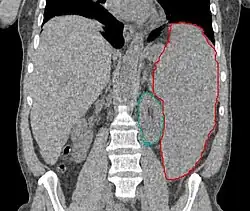

• Patients should be continuously monitored, and fields adjusted with shrinking spleen

• RT should be stopped when therapeutic goal is achieved, rather than when prescription is reached